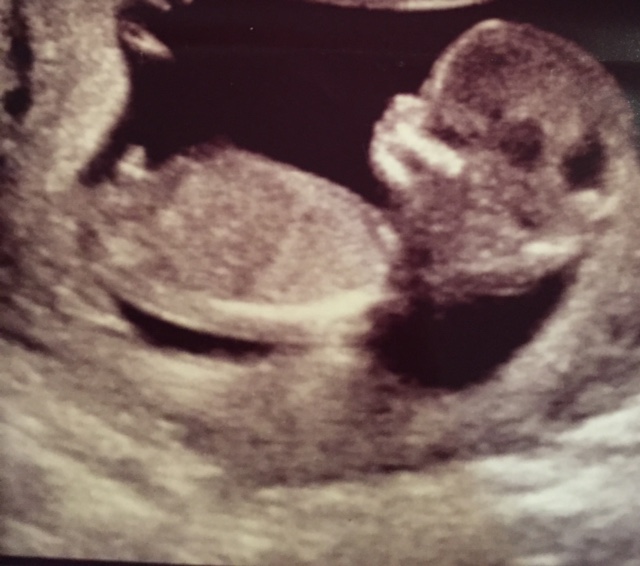

Why are boy nubs all so different from each other?

Hey ladies! Just pondering nubs until my anatomy scan. After seeing so many nubs on the internet, I'm wondering, why do boy nubs differ so much? Girls tend to be all similar: close to the bottom, straight out, some with a fork.

But boys: some are little stacked blobs, some are long straight lines with a bump at the end, some look like hockey sticks or pipes, some stick straight up and some are pretty close to parallel. What the heck? I thought girls were supposed to have the complicated anatomy! Haha.

But here are some examples of what I mean with the different "types":